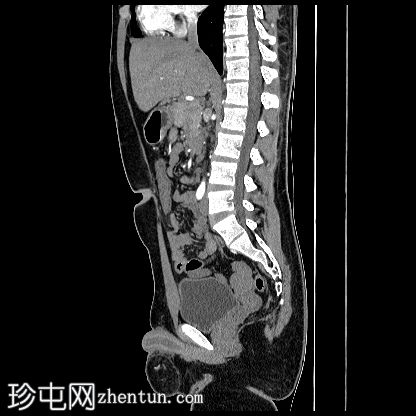

CT

轴位

平扫

1.jpg

阴茎:发育良好。阴茎海绵体和尿道海绵体均存在。

阴囊:双侧均存在,但空虚。

左侧腹股沟深环可见一裂隙,大网膜脂肪由此突出至左侧阴囊。裂隙大小约20毫米。

盆腔左侧可见一形态良好的子宫样结构(57 x 17毫米),开口于前列腺尿道。

右侧睾丸位于盆腔右侧,膀胱与直肠之间。大小:56 x 29 毫米。

左侧睾丸位于盆腔中线左侧,膀胱上方,子宫底旁。该结构附着于从左侧腹股沟管延伸出的索状结构上。大小:38 x 22 毫米。